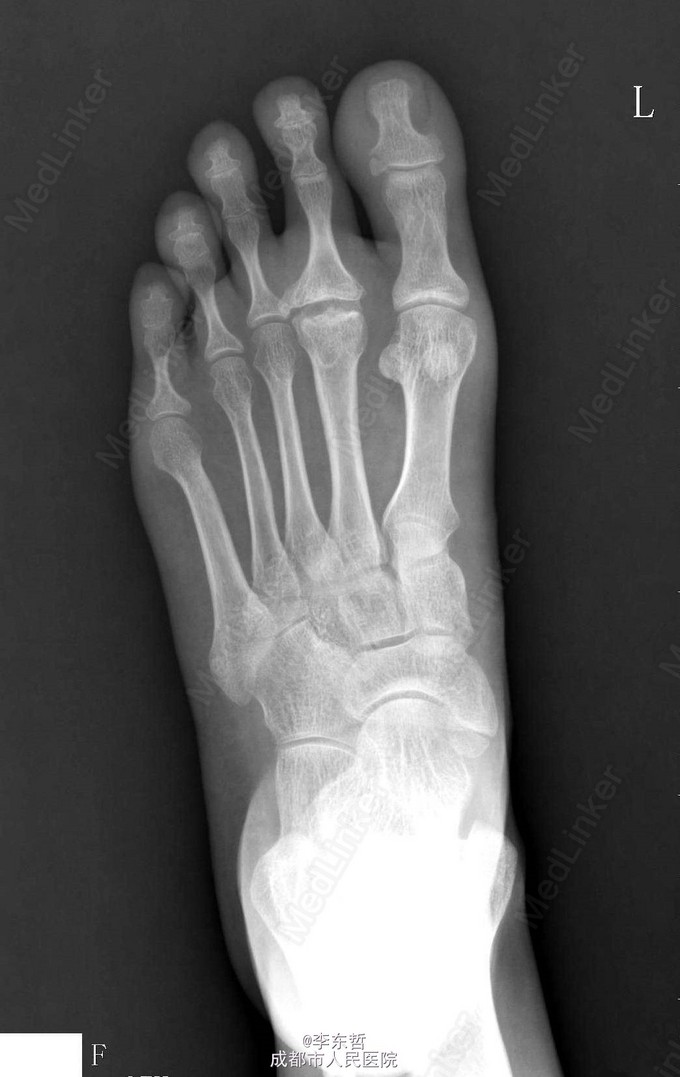

第二跖骨坏死

患者青年女性,因脚底疼痛2月加重3天来院就诊,入院后x线片出现“骨端烟头征”:软骨坏死的X线征之一,正常关节面变模糊,表面参差不齐,如燃烧的烟头样;提示第二跖骨头坏死迹象。